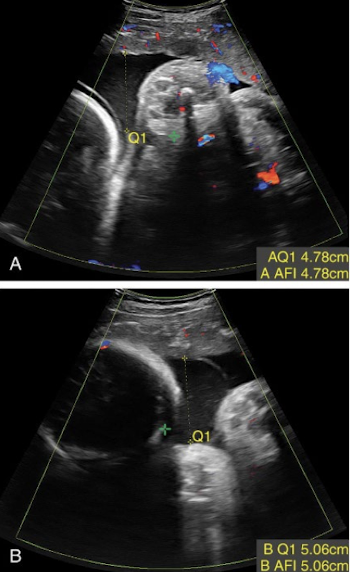

AF measurement method: single largest pocket (MVP)

maximum vertical pocket assessment (MVP)

measure largest pocket in AP

pocket should be clear of fetal parts and umbilical cord

normal single pocket (SP or MVP) values

2 cm < SP < 8 cm

should be between 2-8 cm

abnromal single pocket (SP or MVP) values

oligohydramnios (too little)

SP < 2 cm

polyhydramnios (too much)

SP > 8 cm

how to measure AFI for twins?

have a slightly lower AFI than singleton pregnancies

AFI gives overall assessment for pregnancy not search sac

assess each sac independently

largest vertical pocket is more accurate in polyhydramnios